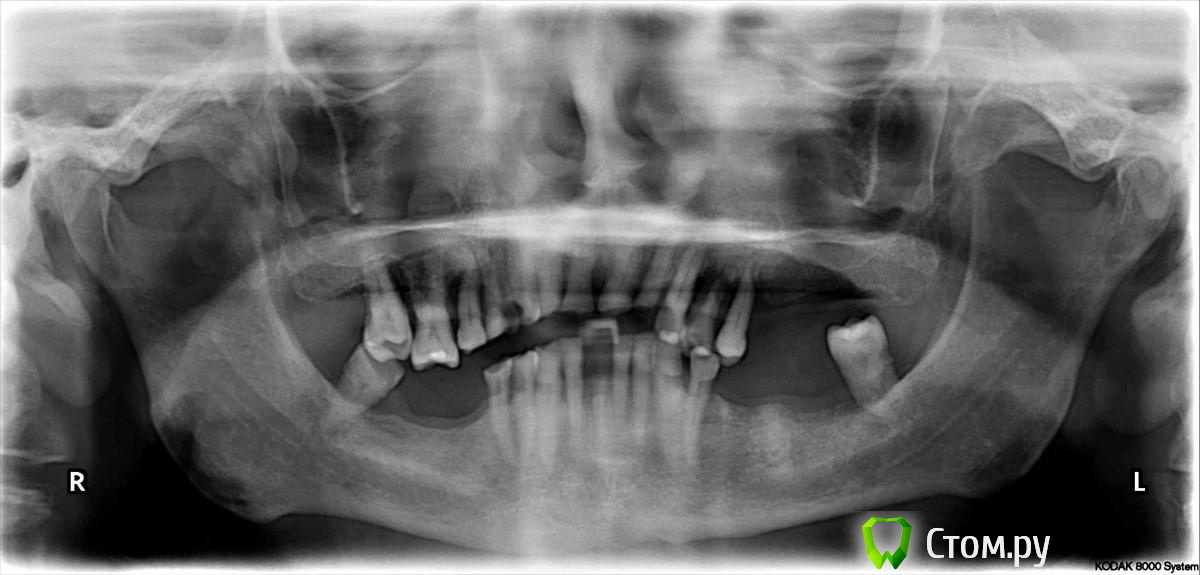

Рытов Станислав Опубликовано 20 января, 2014 Поделиться Опубликовано 20 января, 2014 уважаемые коллеги! хотелось бы совета, кому как видится конечный результат в ситуации на оптг?подвижны 2.4, 2.5, 3.8. на всех зубах абфракционные дефекты почти до пульповой камеры Ссылка на комментарий

gum Опубликовано 21 января, 2014 Поделиться Опубликовано 21 января, 2014 Судя по ОРТО что мы видим: Пародонтит это раз, патологическая стираемость - два, атрофия костной ткани - три.Предлагаю :1. Удалить: 17,16, 15 (необходим прицельный снимок.). 24, 25. Прицельный снимок на 23 для уточнения высоты костной ткани. 2.Определение ЦО 3. Изготовление ваксап на все оставшиеся зубы вч. 4. Эндодонтия оставшихся зубов вч 5. Культевые вкладки при необходимости 6. МК коронки 7. Съемный протез 8. На нч тож самое либо просто съемный Или остеопластика и имплантаты Ссылка на комментарий

doktor vv Опубликовано 22 января, 2014 Поделиться Опубликовано 22 января, 2014 Будь это ваша верхняя челюсть- так же похабно отнеслись ?В стоматологии нет слова похабно,зато есть слово РАЦИОНАЛЬНО.Прогноз для зубов верхней челюсти не благоприятный- и независимо от того шинировать ли с помощью дуги или нет через пару тройку лет придется удалять.Для оценки состояния костной ткани одного панорамного снимка и нескольких прицельных недостаточно-необходимо сделать компьютерную томографию. Ссылка на комментарий

RuStom Опубликовано 22 января, 2014 Поделиться Опубликовано 22 января, 2014 Я бы однозначно удалил 15, 16,17, 24, 25, 38, 48. Кроме того сделал бы прицельные снимки и решил вопрос о сохранении 14, 23.Конечный результат съемные протезы. Количество МК коронок рассчитывал бы в зависимости от состояния зубов, потребностей пациента. Ссылка на комментарий